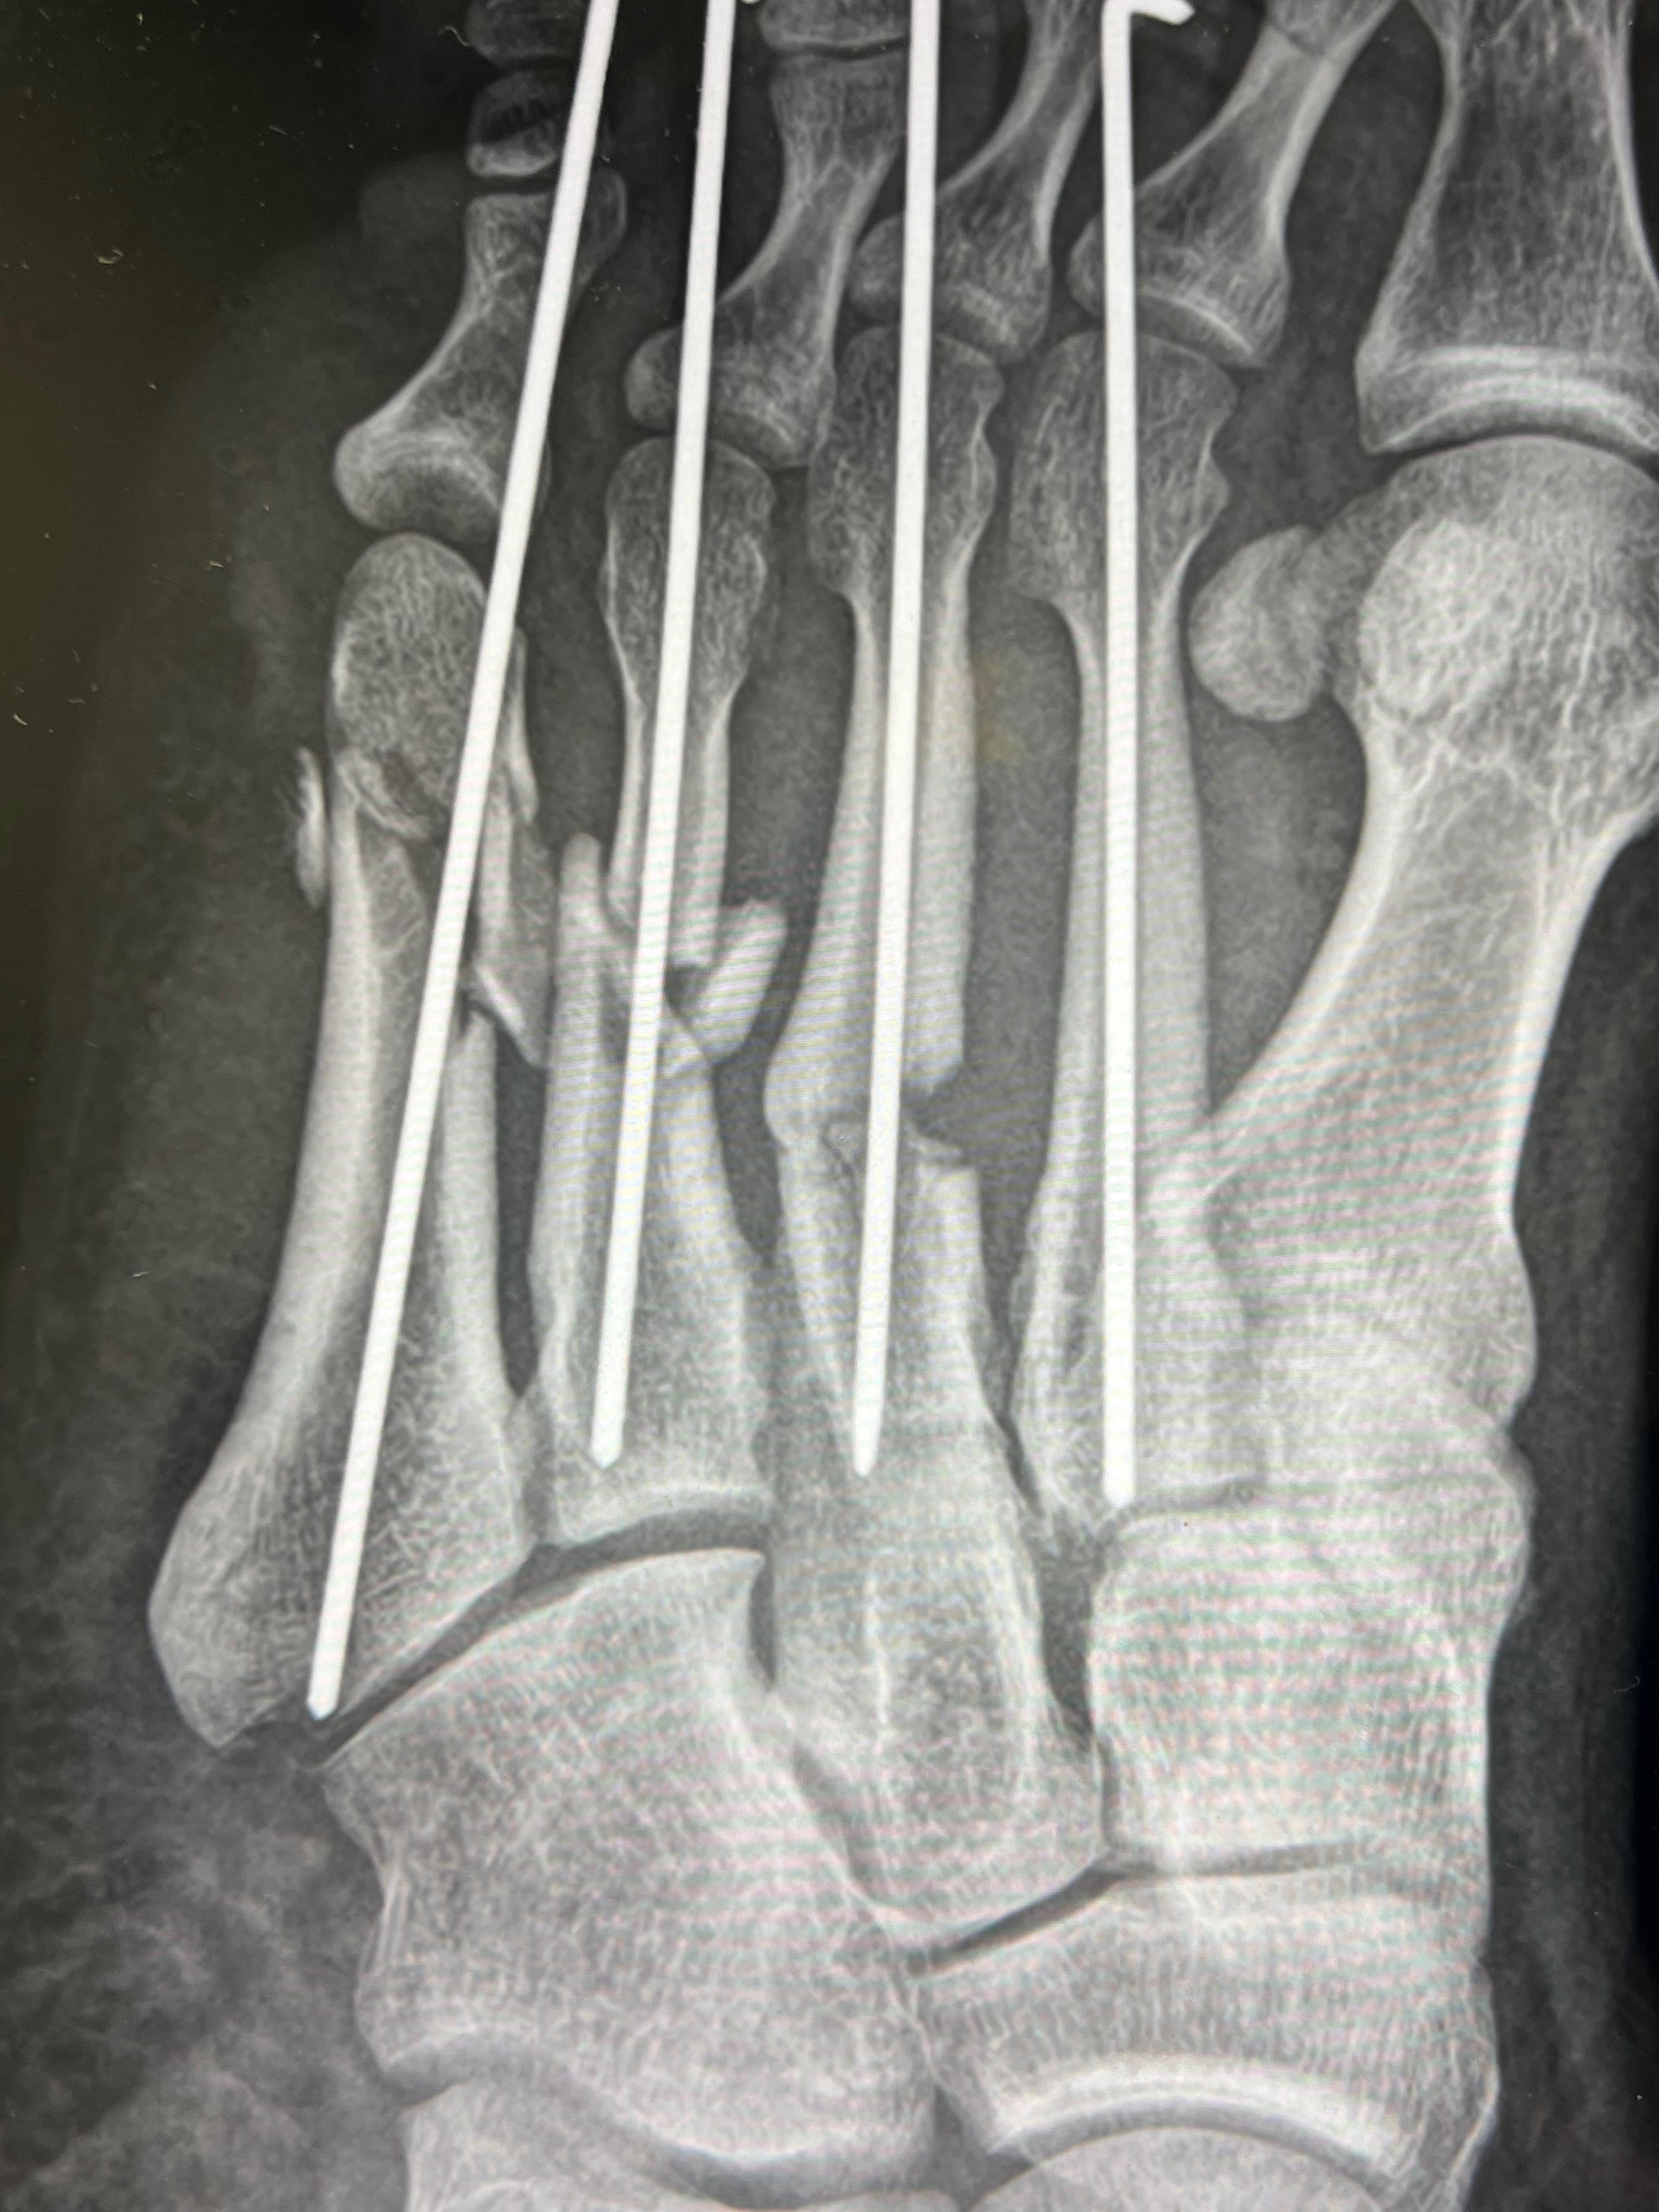

So, back in September, I had a horrible wreck that shattered my foot, broke my wrist, multiple ribs, and knocked me out. Luckily, I did have insurance to cover the initial surgery and accident. It’s been almost 4 months, and I haven’t been able to work, and my foot isn’t healing properly, so they want to go in and do another surgery that’s going to take me out for another 3-6 months.